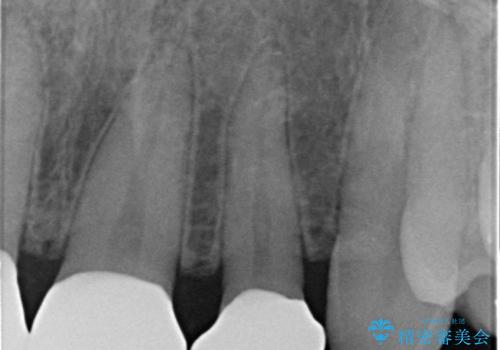

- 前歯の隙間を埋めたいとのことで来院された患者様です。

矯正治療とかぶせ物での治療どちらともご提案したところ、かぶせ物での治療をご希望されたためクラウンでの審美性回復を試みることとなりました。

今回のように、元の歯が小さすぎる場合は矯正治療での審美性回復が難しいことがあります。

形のイメージを反映させた仮歯を調整し、技工士さんと連携して製作したため口元に調和した非常に審美的なクラウンを装着することができました。